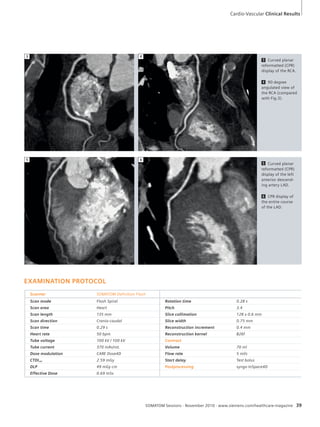

variant vascular anatomy consisting of

the common hepatic artery arising

from the superior mesenteric artery

(Fig. 1 and Fig. 3).

SOMATOM Sessions · November 2010 · www.siemens.com/healthcare-magazine 41

HISTORY

A seven-year-old boy who had been

diagnosed two years prior with fibro-muscular